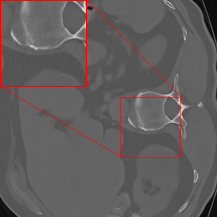

The methodology from DRUNet and its predecessor FFDNet [69] involves segmenting the input image into four distinct corner parts, each processed separately through the network. Zhang et al. [17] utilize images with identically distributed Gaussian noise, allowing for individual denoising of sub-images and recombination without noticeable artifacts at the patch boundaries. However, our application of this strategy in CT results in artifacts at the patch boundaries (cf. Figure 2(c)), showcasing a sudden shift from intense to subtle smoothing with the cropping strategy. This issue may arise because the errors in CT images are not simply Gaussian noise, but rather a more complex mixture of noise types, including Poisson noise that has been log-transformed and then backpropagated via FBP. For mitigating the artifacts, we modify the cropping approach of [69] by implementing padding in the output of the FBP to align with the network architecture. The DRUNet architecture operates solely on images sized as multiples of 24=16superscript24162^{4}=162 start_POSTSUPERSCRIPT 4 end_POSTSUPERSCRIPT = 16 due to its four downsampling steps, whereas the LoDoPaB-CT dataset comprises images of size 362×362362362362\times 362362 × 362, which does not conform to this requirement. To address this, we apply mirror padding to enlarge the images to 368×368368368368\times 368368 × 368 before passing them through the network and subsequently cropping them back to the original size of 362×362.362362362\times 362.362 × 362 . Figure 2 illustrates the suitability of the proposed strategy. (We point out that the image depicted in Figure 2 represents one of the most challenging reconstructions within the dataset.) For the 2016LDCTGC dataset, the images are sized at 512×512512512512\times 512512 × 512, which means they do not need additional padding and can be processed directly by the network.

Figure 2: An example highlighting the distinction between the DRUNet and FFDNet methodology of cropping versus the adapted padding strategy. (a) shows the low-dose FBP, while (b) displays the corresponding ground truth. (c) highlights the artifacts at the patch boundaries resulting from denoising on sub-images, whereas (d) exhibits artifact mitigation achieved through ommiting the partitioning into blocks.